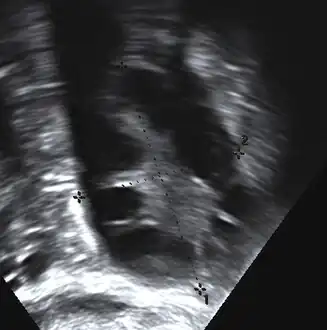

The syndrome acquired its most widely used name due to the common sign on ultrasound examination of multiple (poly) ovarian cysts. These "cysts" are in fact immature ovarian follicles. The follicles have developed from primordial follicles, but this development has stopped ("arrested") at an early stage, due to the disturbed ovarian function. The follicles may be oriented along the ovarian periphery, appearing as a 'string of pearls' on ultrasound examination.[85]

Not every person with PCOS has polycystic ovaries (PCO), nor does everyone with ovarian cysts have PCOS; although a pelvic ultrasound is a major diagnostic tool, it is not the only one.[90] The diagnosis is fairly straightforward using the Rotterdam criteria, even when the syndrome is associated with a wide range of symptoms.[91]

Transvaginal ultrasound scan of polycystic ovary

Polycystic ovary as seen on sonography

- Gynecologic ultrasonography, specifically looking for small ovarian follicles. These are believed to be the result of disturbed ovarian function with failed ovulation, reflected by the infrequent or absent menstruation that is typical of the condition. In a normal menstrual cycle, one egg is released from a dominant follicle – in essence, a cyst that bursts to release the egg. After ovulation, the follicle remnant is transformed into a progesterone-producing corpus luteum, which shrinks and disappears after approximately 12–14 days. In PCOS, there is a so-called "follicular arrest"; i.e., several follicles develop to a size of 5–7 mm, but not further. No single follicle reaches the preovulatory size (16 mm or more). According to the Rotterdam criteria, which are widely used for diagnosis of PCOS,[10] 12 or more small follicles should be seen in a suspect ovary on ultrasound examination.[21] More recent research suggests that there should be at least 25 follicles in an ovary to designate it as having polycystic ovarian morphology (PCOM) in women aged 18–35 years.[94] The follicles may be oriented in the periphery, giving the appearance of a 'string of pearls'.[95] If a high-resolution transvaginal ultrasonography machine is not available, an ovarian volume of at least 10 ml is regarded as an acceptable definition of having polycystic ovarian morphology. rather than follicle count.[94]

Ultrasound findings in PCOS include enlarged ovaries with peripheral follicles in a "string of pearls" configuration.